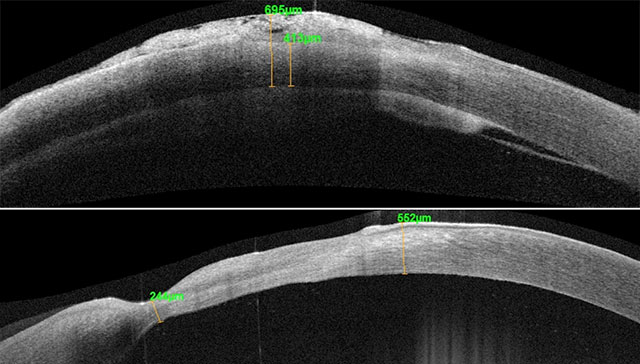

科室建立了优化的感染性及免疫性角膜炎诊疗流程,采用“无创、无接触-无创、接触-有创”的阶梯式检查模式,利用眼前段照相机、眼前段OCT【图1】、角膜共焦显微镜【图2】对角膜病灶的形态、变化、浸润深度、溃疡深度进行记录,与微生物室建立“感染性眼病微生物沟通平台”,为病原体的诊断与鉴别提供有力的佐证。另外,角膜专科联手屈光专科,采用CorvisST 和 Pentacam 角膜地形图对圆锥角膜进行早期筛查,并提供配镜、RGP验配、复诊及手术治疗等多项递进式治疗手段。

图1 眼前段OCT可高清显示角膜病灶深度、角膜最薄处厚度等